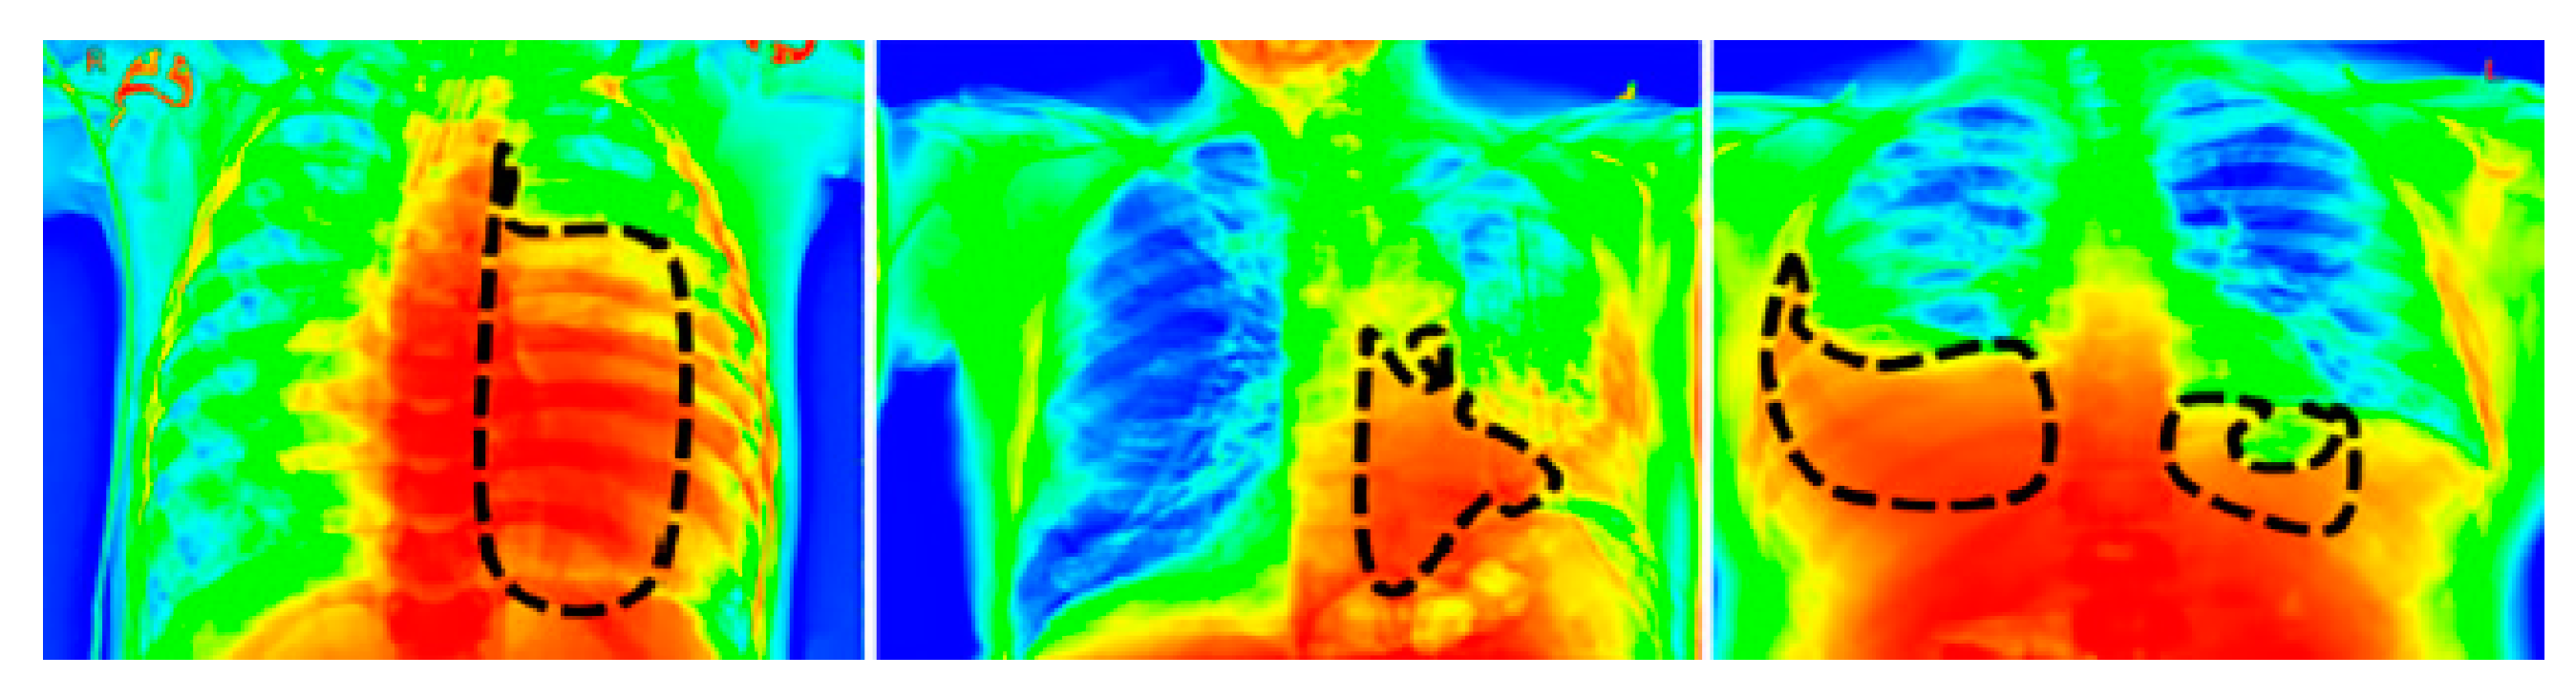

3.4. Image Segmentation